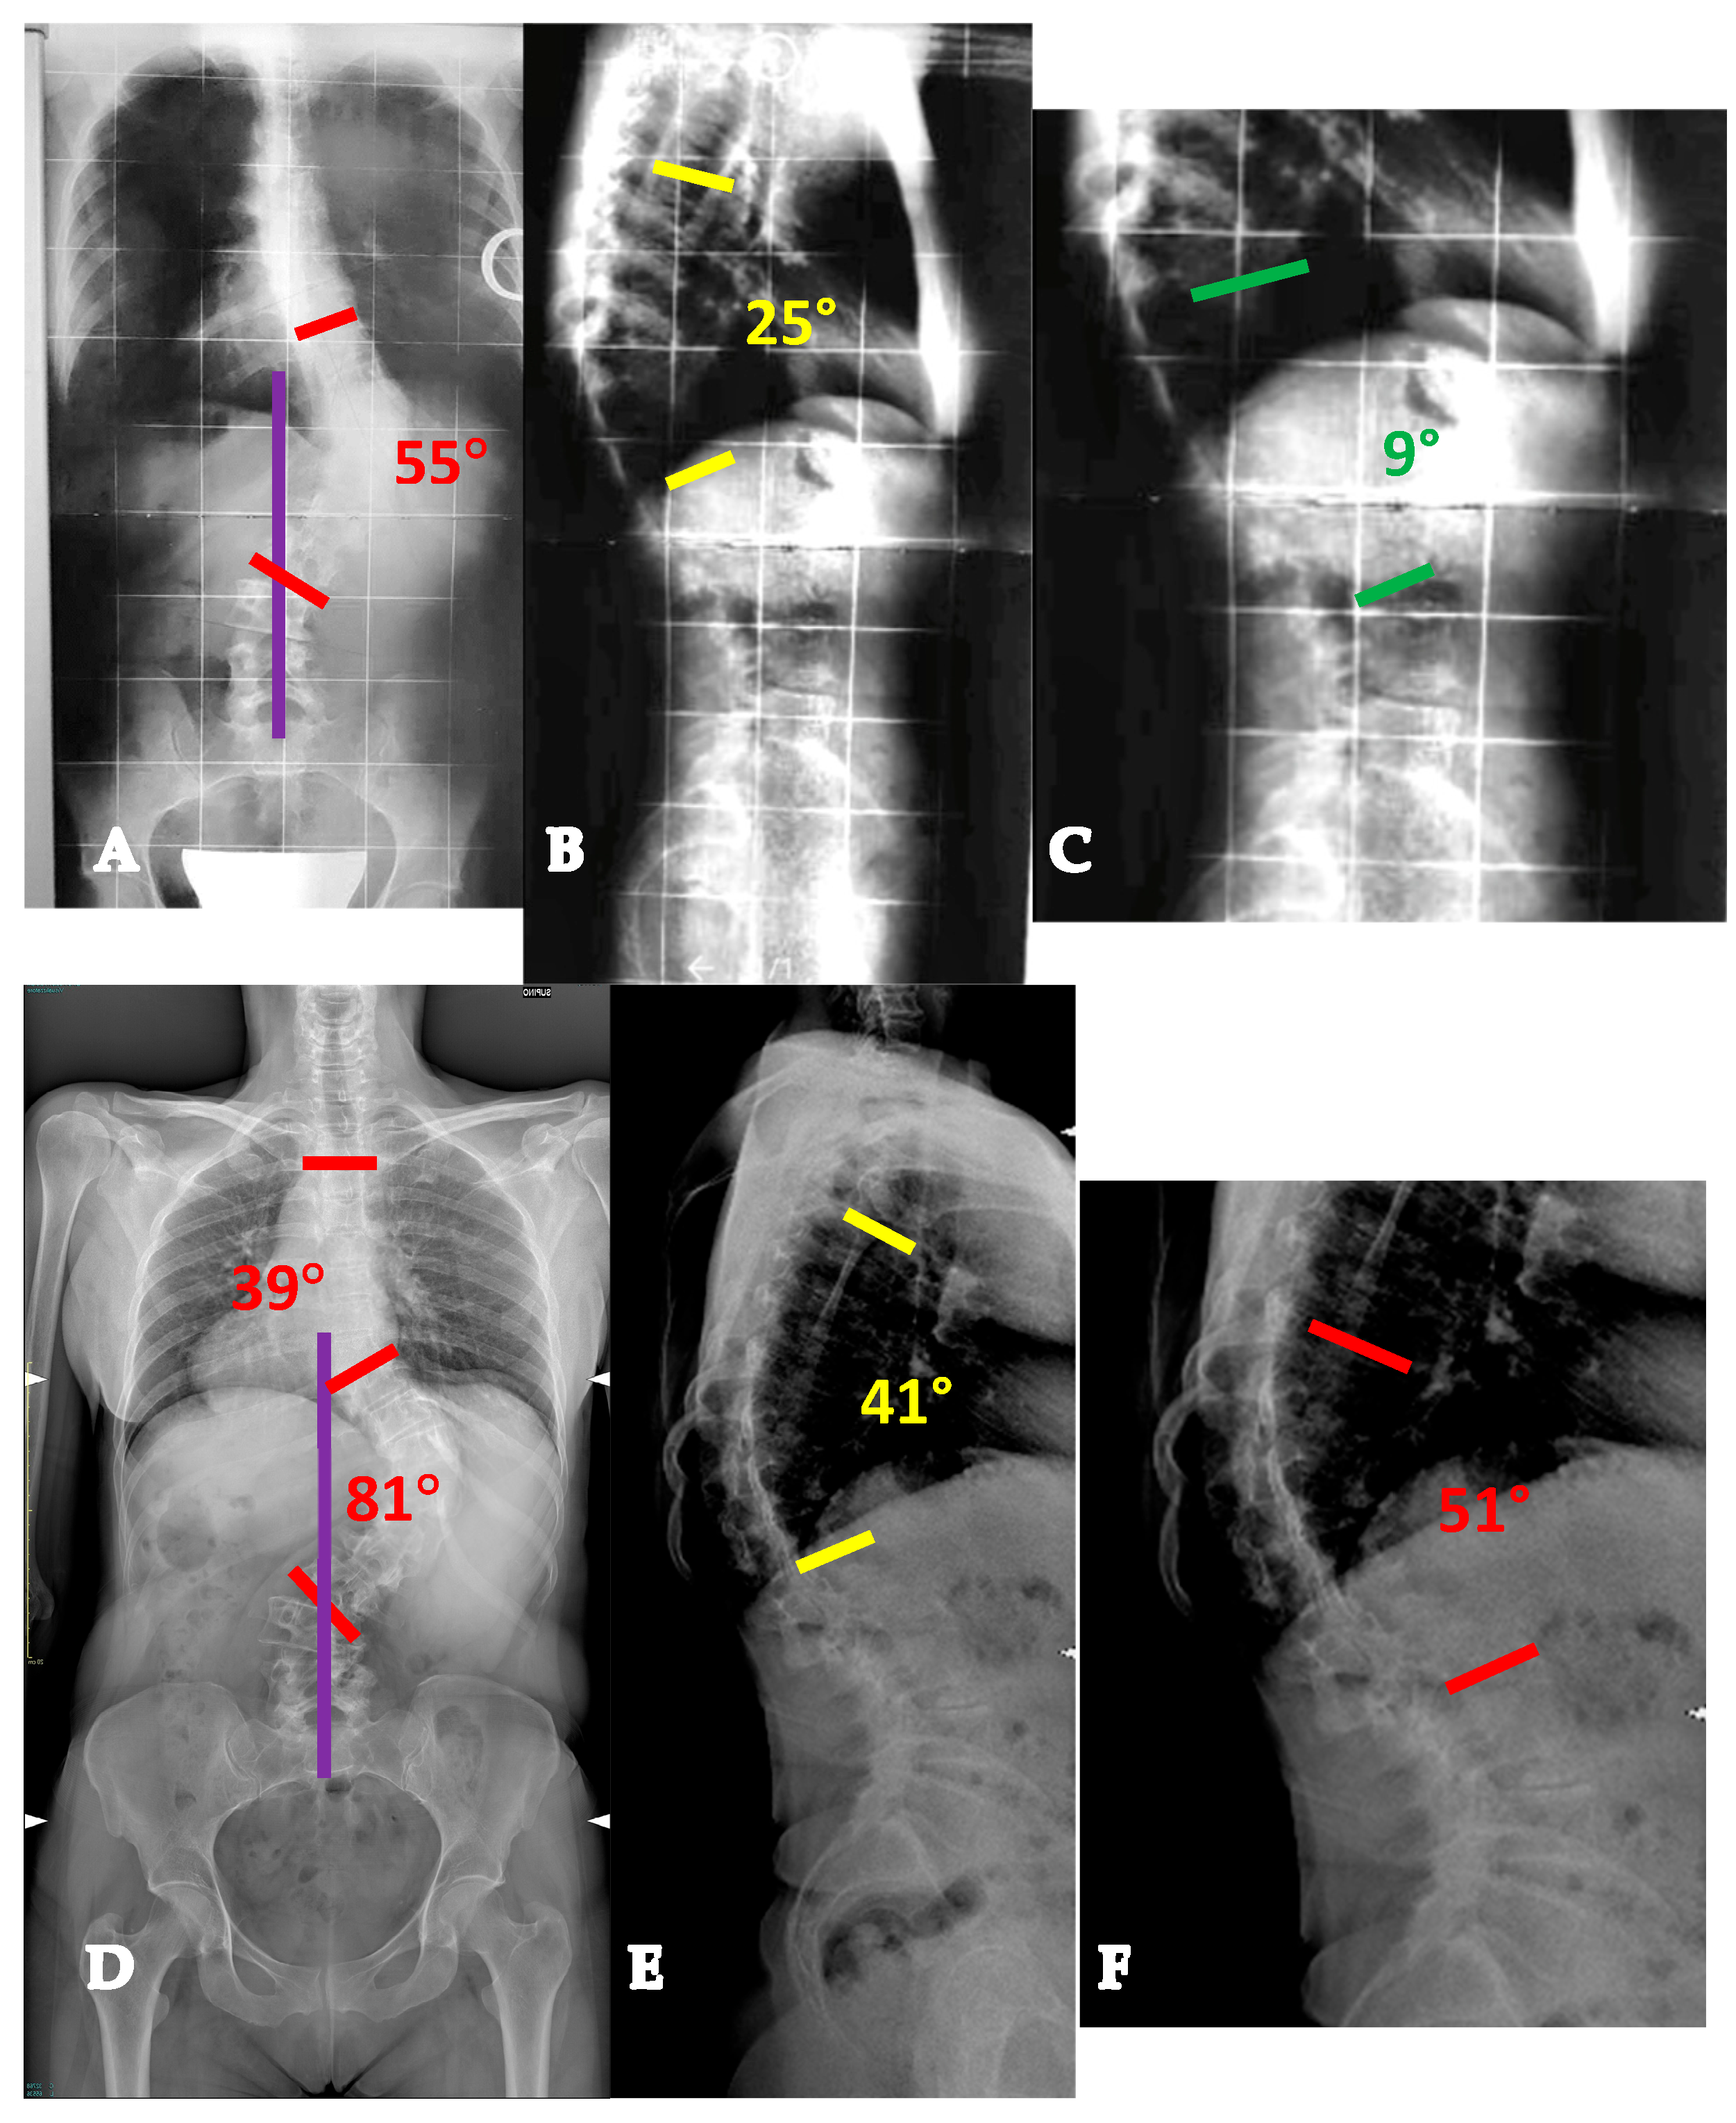

- For curves < 90° OR ≥90° and with a flexibility index > 15% (YADIS 2A), a combination of strategies with an all-posterior approach, already published by the authors under the acronym HiPoAD (High-Density Pedicle Screws, Ponte Osteotomies, Asymmetric Rods Contouring, Direct Vertebral Rotation) [10], may be sufficient to address the deformity. In particular, high-density constructs are preferrable in order to dissipate the corrective forces on every level and decrease the pull-out risks. Then, an aggressive posterior release based on multiple asymmetric Ponte osteotomies is of paramount importance, in order to allow an optimal deroto-translation over two asymmetrically contoured rods (Figure 3) [10,11].

- For curves ≥ 90° AND with a flexibility index < 15% (YADIS 2B), the HiPoAD technique, even though it proved to be effective for this kind of curve when addressed during adolescent years [12], may not be powerful enough for YAdIS 2 patients. These cases should be addressed with a three-columnar approach. One strategy could be to adopt three-column osteotomies like VCR. A possible alternative, in order to avoid the risks of a three-column osteotomy, is to perform a three-columnar release through a combined approach: an anterior thoracoscopic release (wide resection of anterior longitudinal ligament and multiple periapical discectomies), followed by a posterior column release based on multiple Ponte Osteotomies and a posterior correction (VT-HiPoAD, Videothoracoscopic release—HiPoAD) (Figure 4).